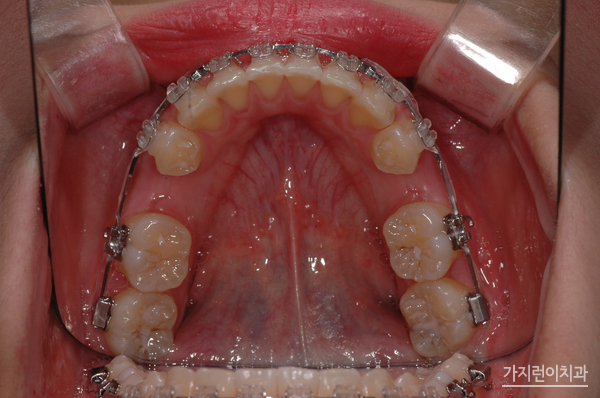

미니스크류는 인체에 해롭지 않은 나사형태로 제작된 미니 임플란트라고 보실 수 있겠습니다. 잇몸 사이 뼈에 식립해 치아를 필요한만큼 이동시키는 힘을 더하는 방식으로 치아이동을 좀 더 빠르게 도와주는 보조장치입니다. 국소마취 후 진행되기 때문에 따로 절개를 하지 않으며 출혈도 적고 통증도 적어 회복속도가 빠르다는 장점도 있습니다. 또한 잇몸이 많이 보인다거나 부분교정이 필요한는 경우 주로 사용되는데 돌출입을 해결할 때 많이 이용되고 있습니다. 이 경우 턱뼈 안에서 치아들을 뒤로 이동시키는 지지대로서의 역할을 해주기 때문에 발치교정이나 양악수술 없이도 돌출입교정에 효과적일 수 있는데요. 중요한 일정을 앞두고 있거나 직업적으로 대인관계가 중요한 서비스직종의 직장인이라면 염두해볼 수 있겠습니다.

위 환자분들의 경우 1년 8개월의 대장정 끝에 치료과정이 끝나셨습니다. 상하악의 이동을 잘 조절해 골격적인 밸런스도 마무리되셨는데요. 치아교정을 전문적으로 다루고 있는 서울가지런이치과 교정과 의원인만큼 심한 거미스마일 증상과 돌출입 증상도 무리없이 해결했답니다. 오래도록 안정된 결과를 누리고 있는 이 케이스! 걱정말고 서울가지런이치과 교정과 의원을 방문해 보시기 바랍니다.